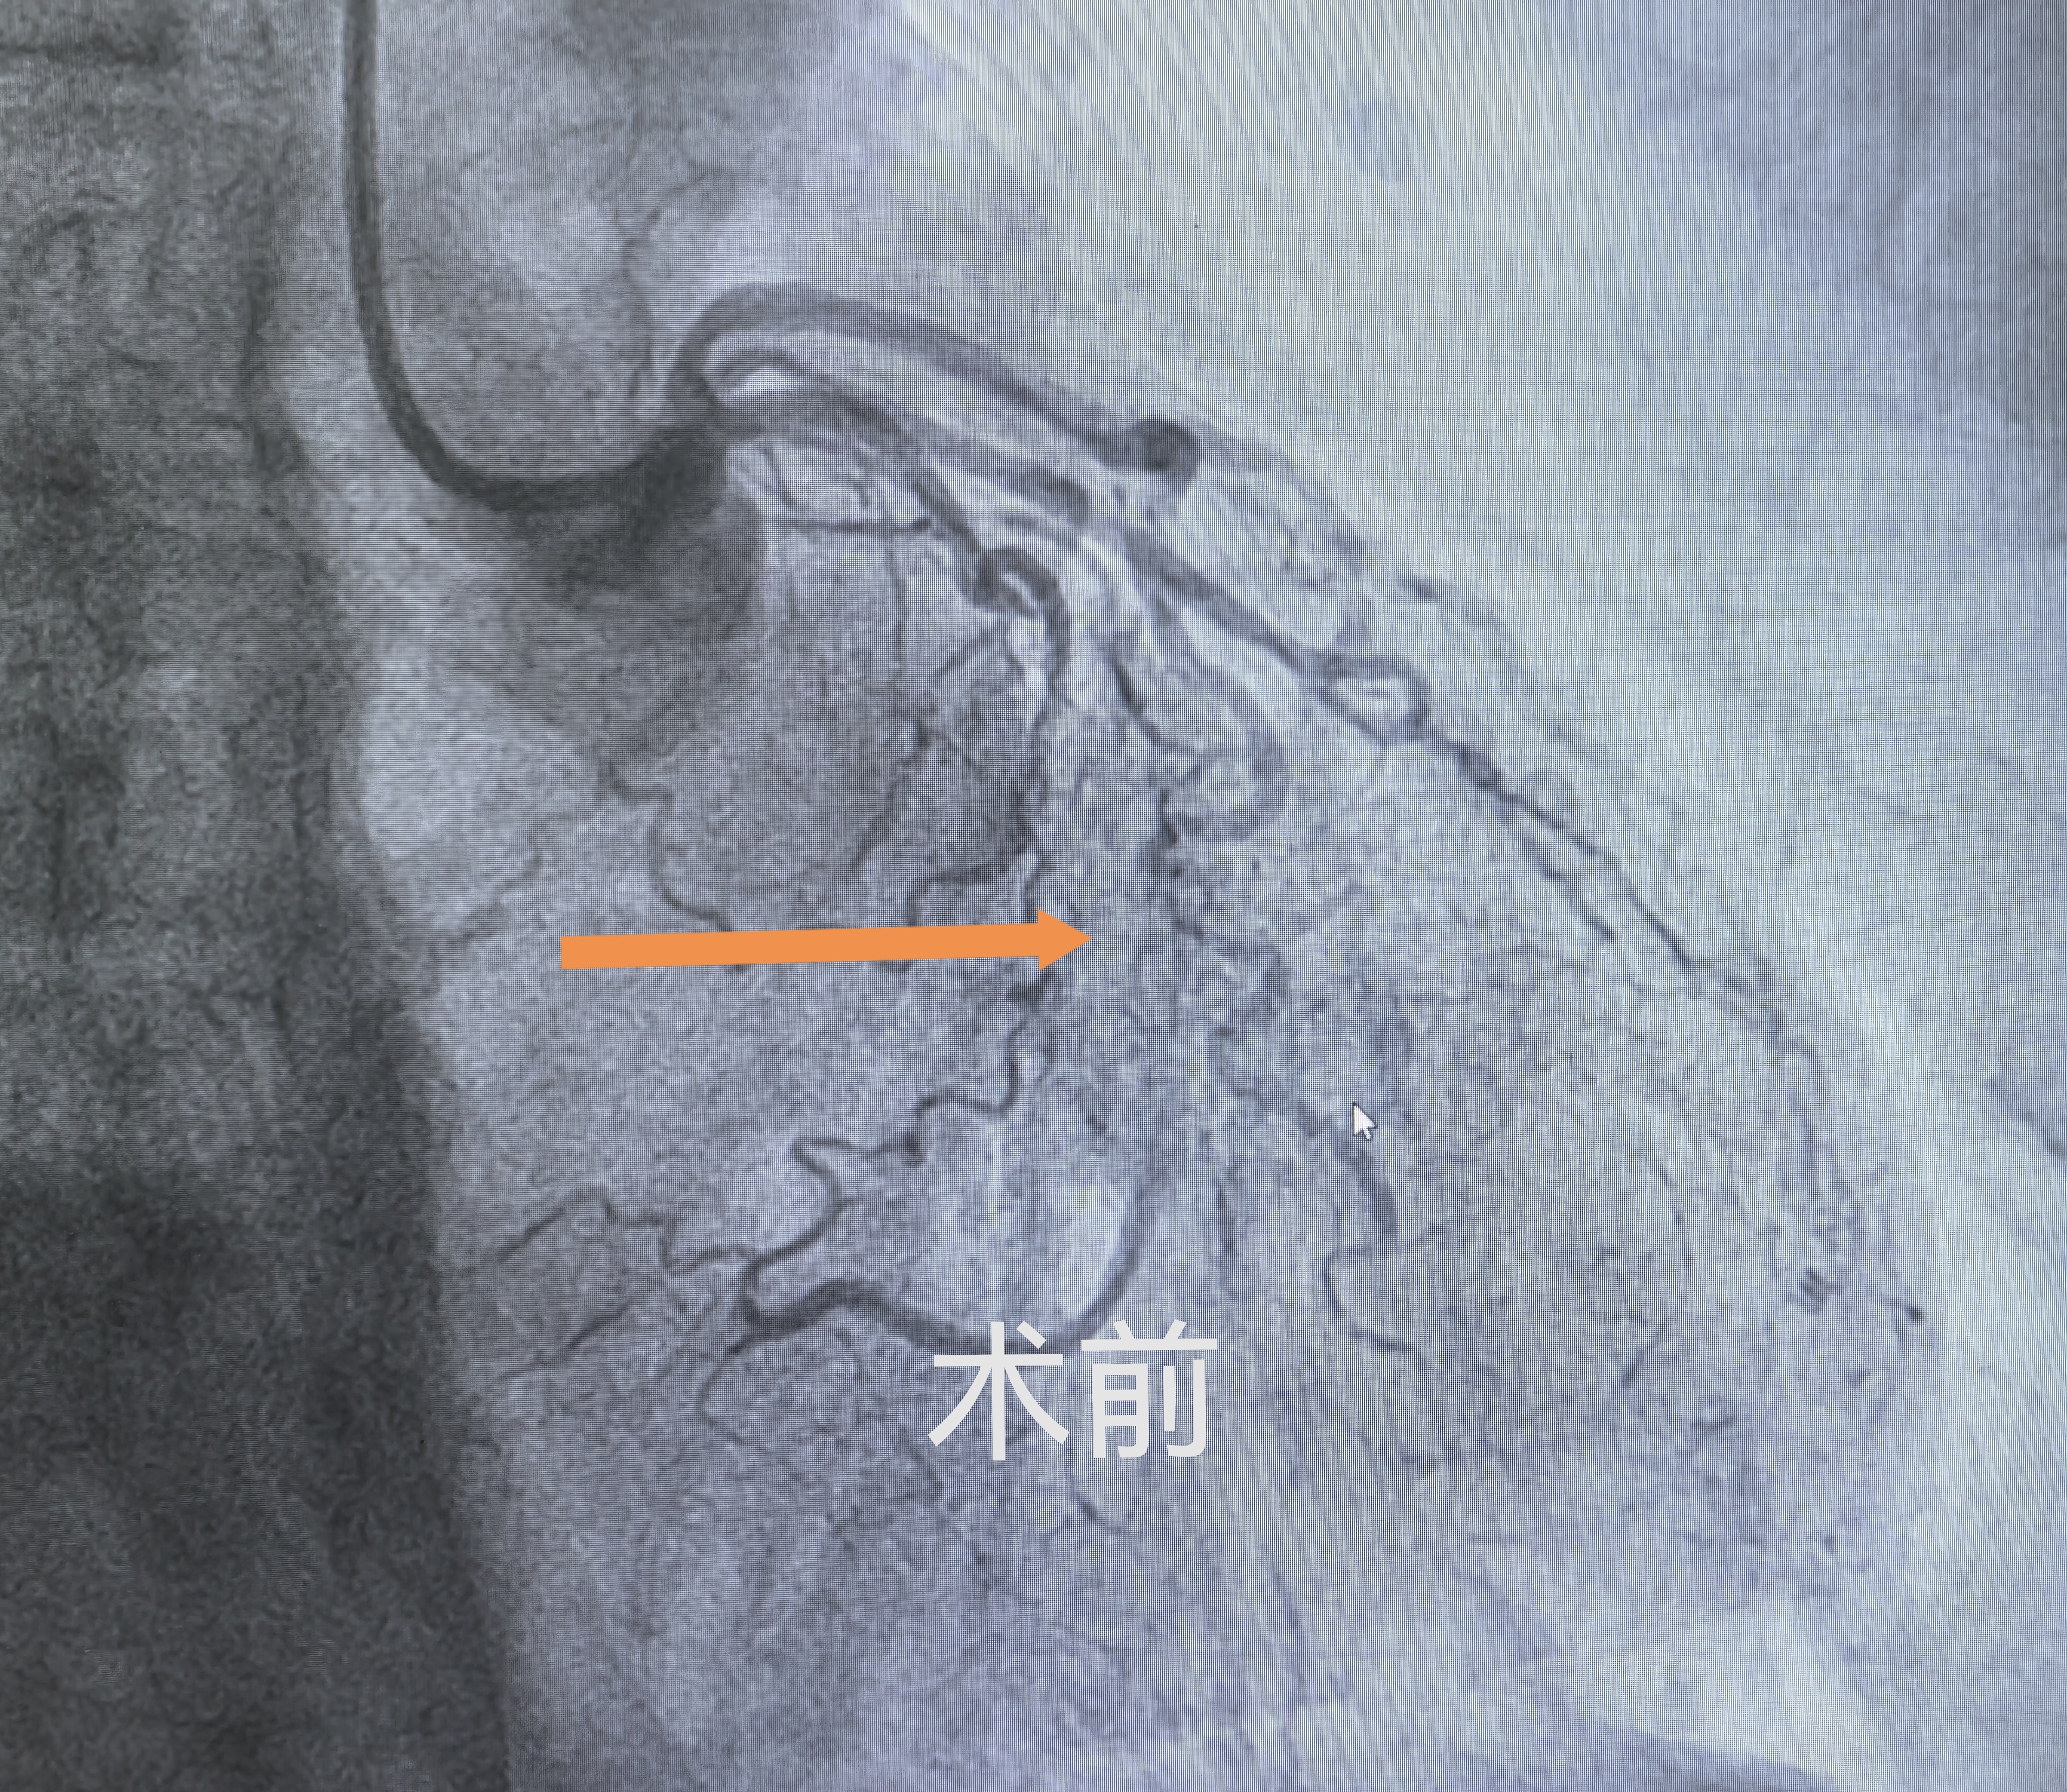

基于这一判断,团队决定为李大爷实施冠脉造影检查——这项被称为冠心病诊断“金标准”的检查,可清晰呈现冠脉血管形态、狭窄程度及闭塞位置,为治疗方案制定提供精准依据。检查结果印证了医生的判断:李大爷的回旋支近段100%完全闭塞,且伴有重度钙化,仅靠微弱侧支循环勉强供血,远端管腔条件极差;同时,右冠状动脉近段也存在80%的严重狭窄,同样伴随钙化。冠脉钙化如同血管内的“硬石头”,不仅会让血管壁变硬、管腔变窄,还会大幅提升治疗难度,一旦斑块破裂形成血栓,急性心肌梗死便会接踵而至。彼时的李大爷,心脏两条关键血管均亮起“红灯”,病情已到刻不容缓的地步。

危急关头,牛锋主任带领介入团队争分夺秒,迅速敲定精准介入治疗方案。手术中,面对100%闭塞且重度钙化的血管,操作难度极大。牛锋主任凭借丰富的临床经验与精湛的操作技术,操控超滑导丝反复试探、精准穿梭,最终成功穿透回旋支闭塞端,抵达远端血管,顺利打通这条“生命通道”。随后,团队精准选用药物涂层冠脉球囊扩张血管,搭配药物洗脱支架系统支撑血管,彻底解决血管闭塞难题,让冠脉血流瞬间恢复通畅,成功化解致命危机。